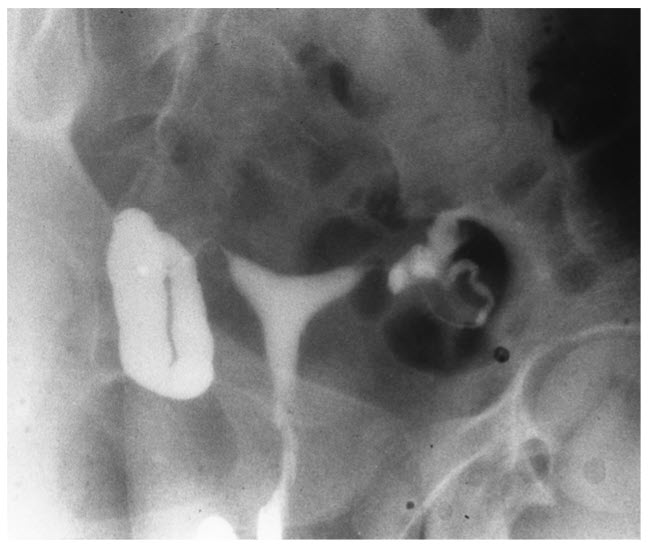

Hysterosalpingography is an important tool in the evaluation of infertility. It provides information regarding the shape of the uterine cavity and the patency of the tubes. Tubal factors, which may result from sexually transmitted diseases, are an important cause of infertility. The figure displays bilateral hydrosalpinx and clubbing of the tubes, with no evidence of spillage into the peritoneal cavity. The uterine cavity appears normal.